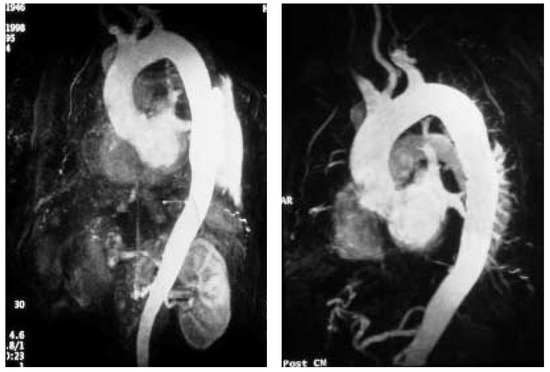

Une patiente de 31 ans souffrant d’une cardiopathie congénitale consulte car elle souhaite une grossesse [...]